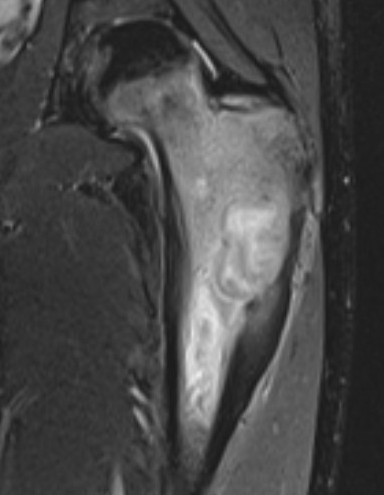

MRI

Lucent lesion with nidus or calcification

Spinal lesion

- bone expansion

- intralesional stippled ossification